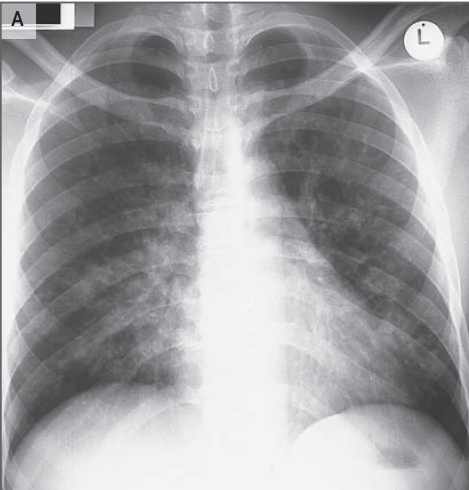

En el examen, la temperatura era de 37,4 ° C; los otros signos vitales y la saturación de oxígeno eran normales. El examen oftalmológico reveló una agudeza visual de 20/20 en el ojo derecho y 20/400 en el ojo izquierdo. Las pupilas eran iguales, redondas y reactivas, con un defecto pupilar aferente izquierdo. Resultados de las pruebas de color visión con placas de color de Ishihara fueron normales en el lado derecho (8/8 correctamente identificados) y 0/8 de la izquierda. La presión intraocular era 13 mm Hg en el lado derecho y 11 mm Hg a la izquierda. Examen con lámpara de hendidura reveló segmentos normales anteriores bilateralmente. El examen de la motilidad extraocular reveló plena movilidad en el ojo derecho; el ojo izquierdo tenía aducción limitada, supraducción y infraducción, con intorsion mínimo en intento de secuestro (Figura 2 ).

Figura 2

Fotografías de los ojos del paciente.

En la mirada primaria (Panel C) hay leve ptosis del párpado superior izquierdo.El ojo izquierdo tiene leve déficit de elevación (Panel A), aducción (Panel B), y depresión (Panel E), y no tiene abeducción (PanelD).